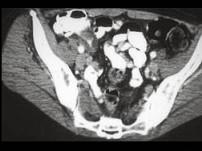

问题 男,42岁,右下腹痛、腹胀半年,无浅表淋巴结肿大,影像检查如图,最可能的诊断是 ( )

选项 A.淋巴瘤 B.结肠癌 C.Crohn氏病 D.肠结核 E.腹膜后纤维化

答案 C